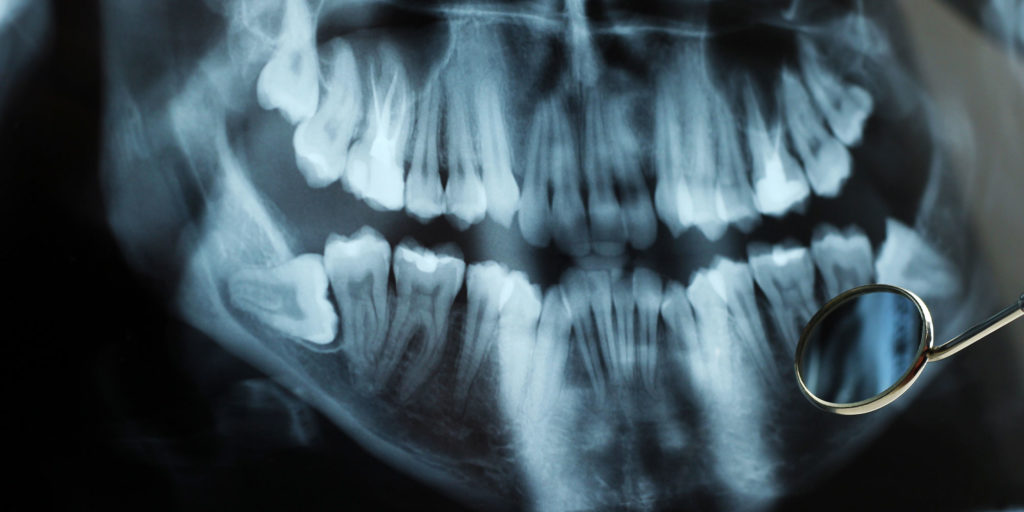

impacted wisdom tooth xray

impacted wisdom teeth graphic